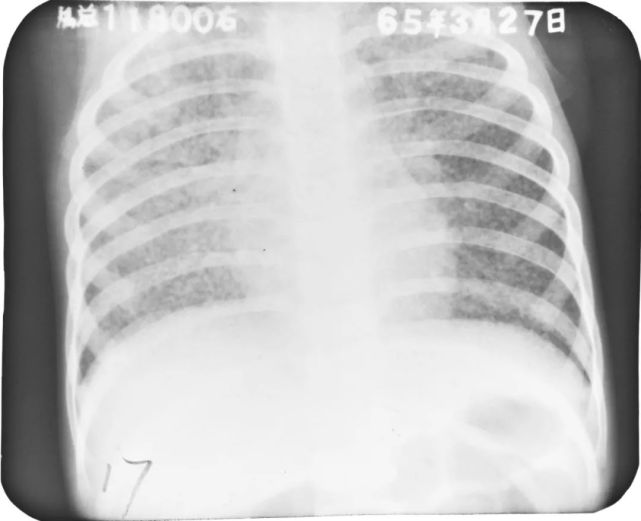

婴幼儿肺炎

图片

胸部正位片示:两肺内带及左肺下野可见不规则的小片状或斑片状边缘模糊的致密阴影,阴影密度不均,局部可见支气管充气征